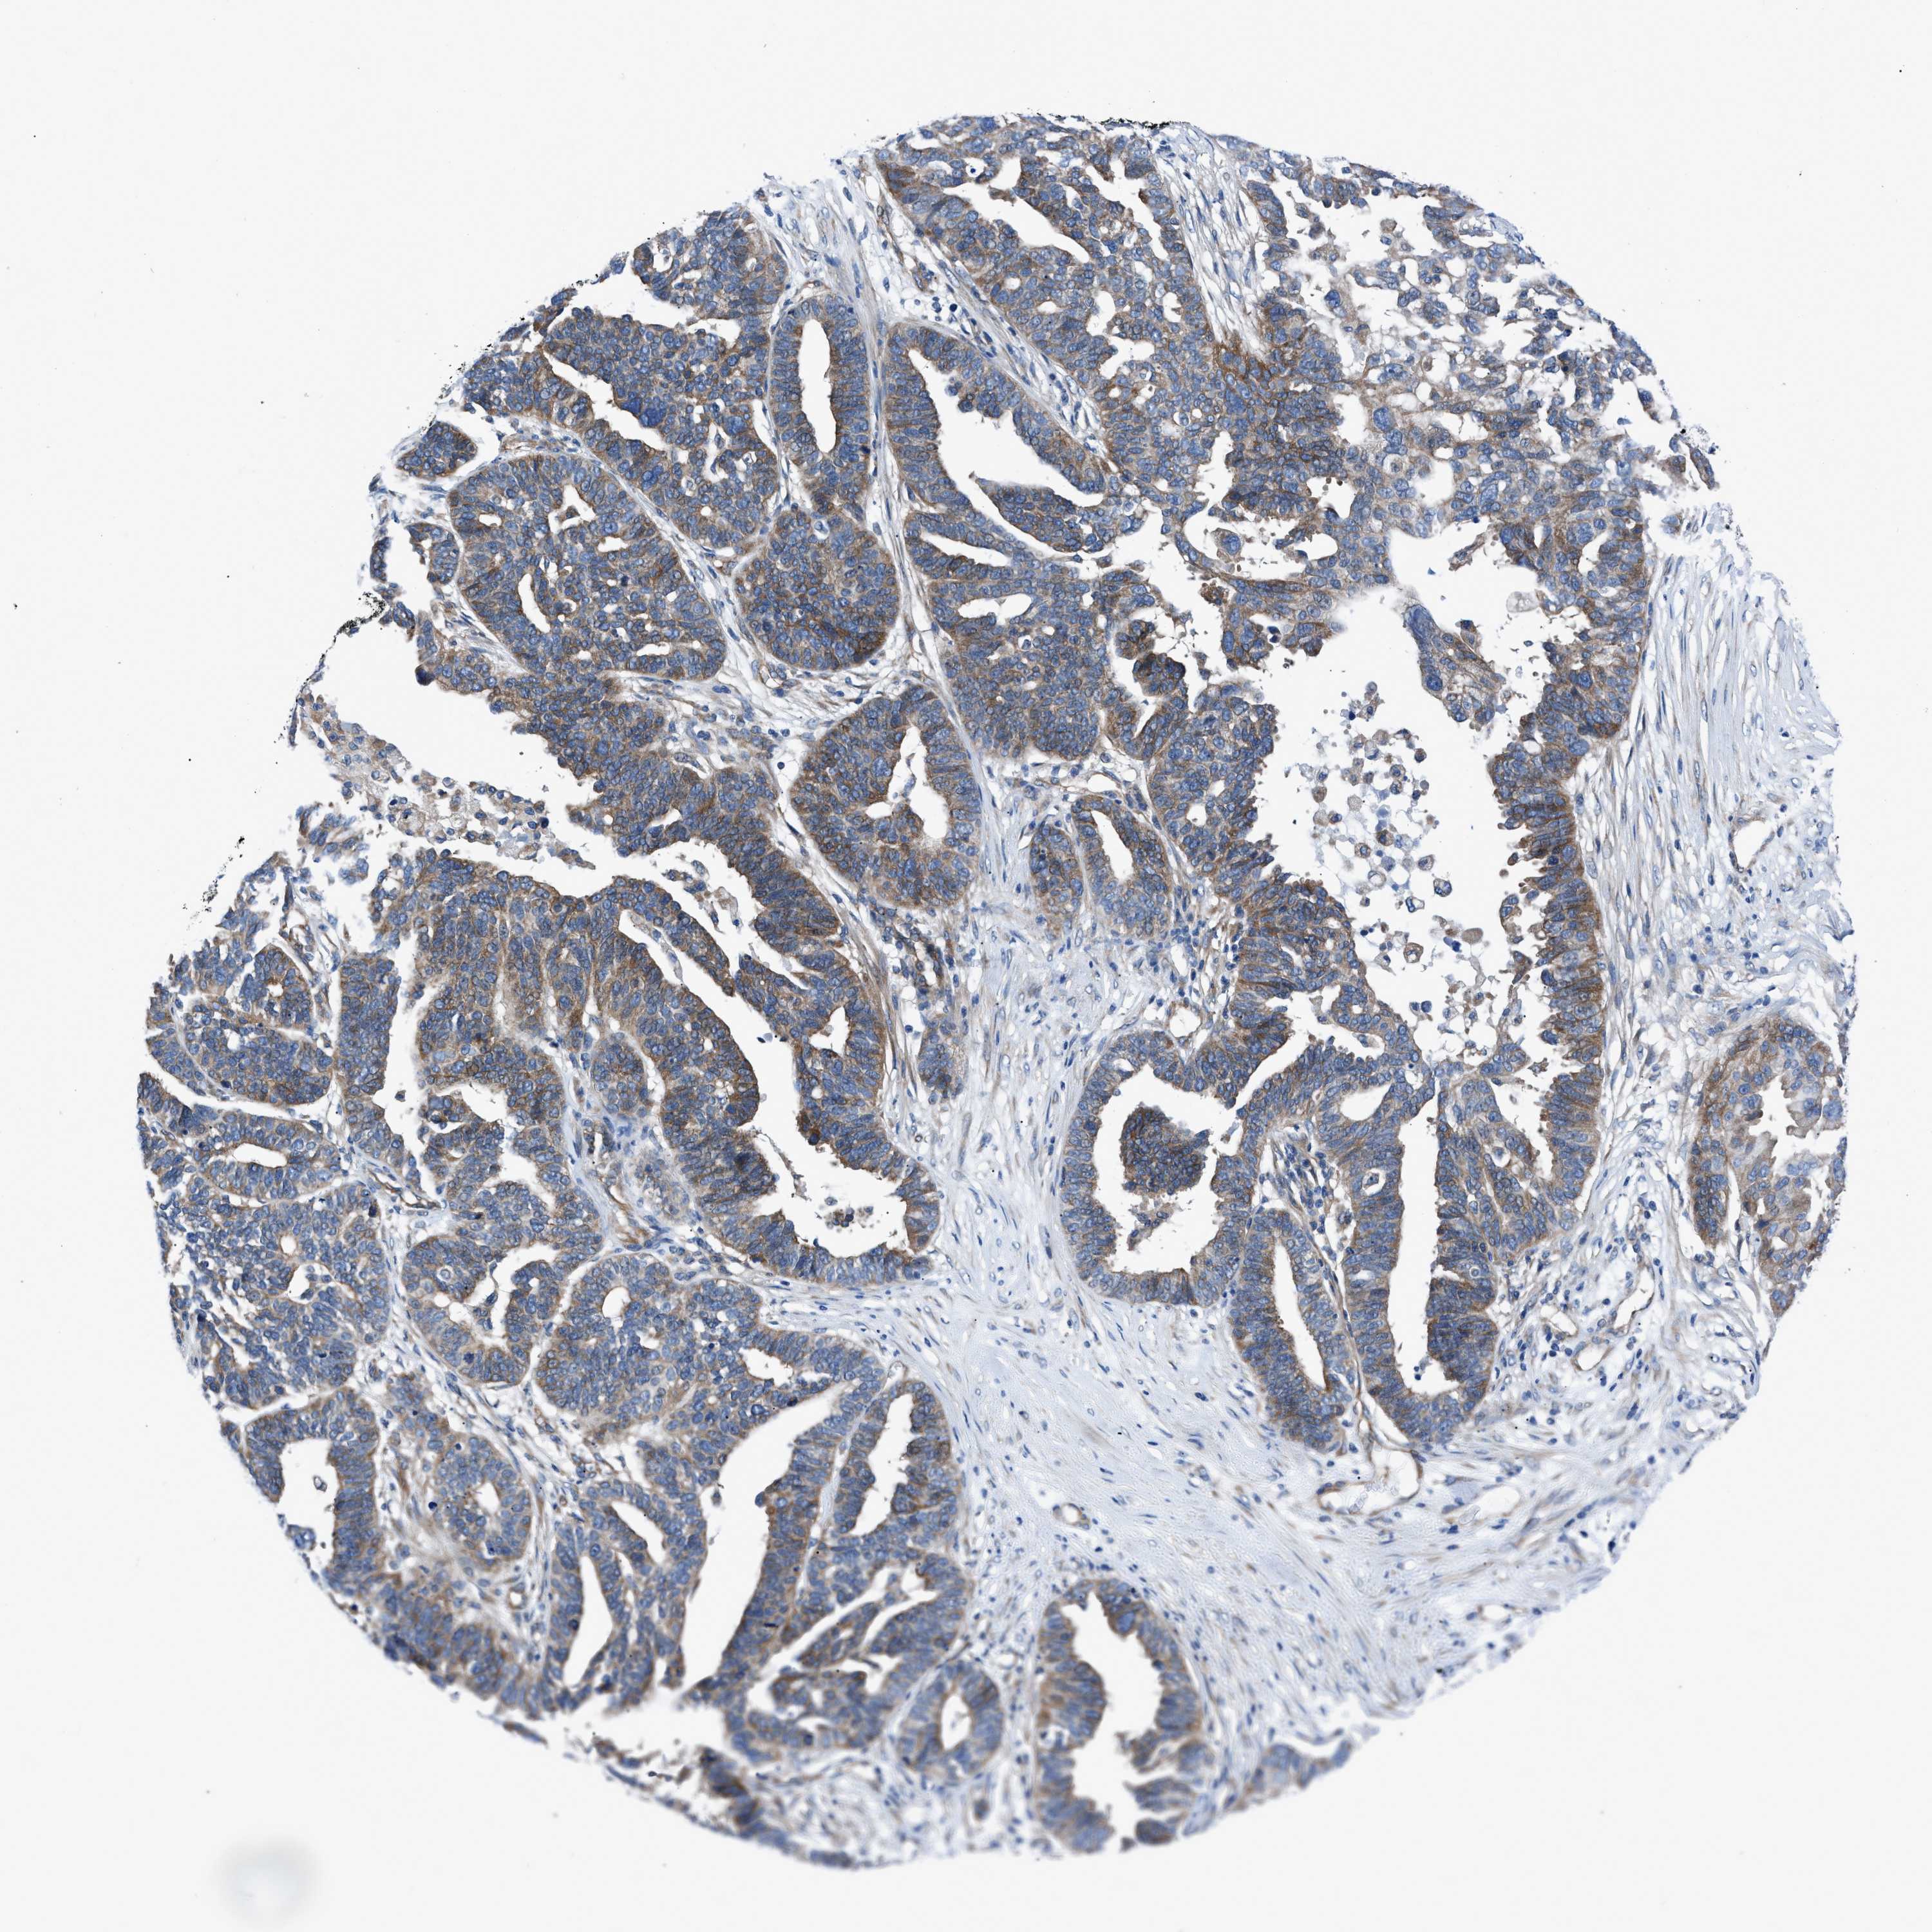

OVARIAN CANCER - Protein expressioni

A mouse-over function shows sample information and annotation data. Click on an image to view it in a full screen mode. Samples can be filtered based on level of antibody staining by selecting one or several of the following categories: high, medium, low and not detected. The assay and annotation is described here.

Note that samples used for immunohistochemistry by the Human Protein Atlas do not correspond to samples in the TCGA dataset.

Antibody stainingi

Antibody staining in the annotated cell types in the current human tissue is reported as not detected, low, medium, or high, based on conventional immunohistochemistry profiling in selected tissues. This score is based on the combination of the staining intensity and fraction of stained cells.

Each image is clickable and will lead to virtual microscopy that enables deeper exploration of all samples and also displays staining intensity scores, fraction scores and subcellular localization as well as patient and tissue information for each sample.

Antibody HPA016605

Staining

High

Medium

Low

Not detected

Intensity

Strong

Moderate

Weak

Negative

Quantity

>75%

75%-25%

<25%

None

Location

Nuclear

Cytoplasmic/membranous

Cytoplasmic/membranous,nuclear

Cystadenocarcinoma, serous, NOS

Carcinoma, endometroid

Cystadenocarcinoma, mucinous, NOS

Carcinoma, NOS